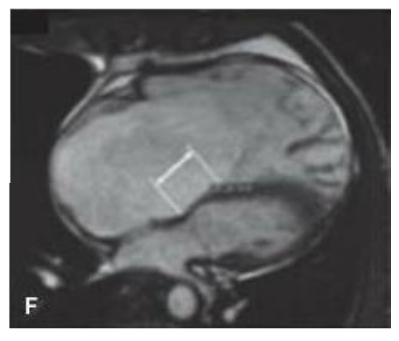

Considerando a patologia exemplificada na figura a seguir, é correto afirmar que, em alguns casos, a confecção de uma anastomose cavopulmonar bidirecional pode ser benéfica.

O caso que melhor exemplifica uma situação benéfica é

Sobre a patologia ilustrada na figura a seguir, assinale a alternativa correta.